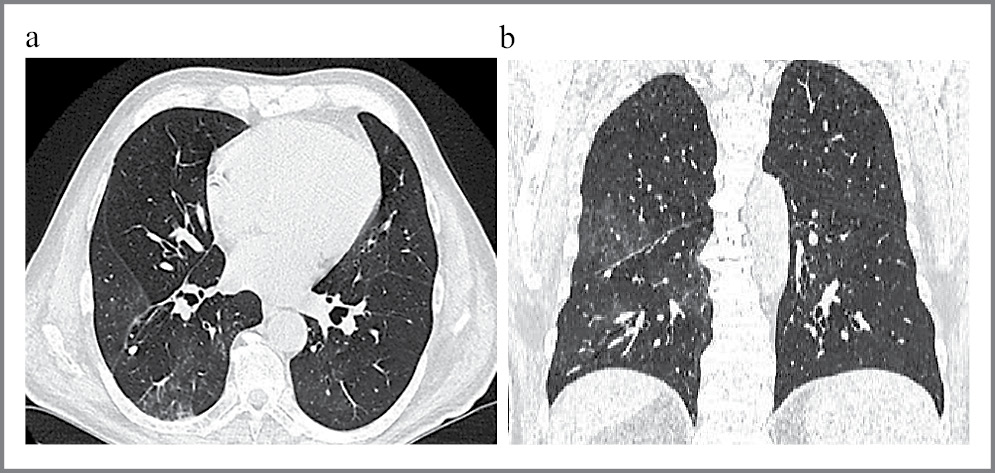

Выполнена повторная КТ легких через 16 дней, на которой определялись множественные очаговые инфильтративные изменения без динамики по сравнению с предыдущим исследованием (рис. 2, a, b).

Рис. 2: а – аксиальная проекция; b – фронтальная проекция. КТ легких первого пациента до операции. Отмечаются множественные участки затемнения по типу «матового стекла».

Через месяц после операции пациент выполнил контрольные снимки КТ органов грудной клетки. На снимках признаки пневмонии полностью регрессировали (рис. 4, a, b.)

Рис. 4: а – аксиальная проекция; b – фронтальная проекция. КТ легких через месяц после операции.